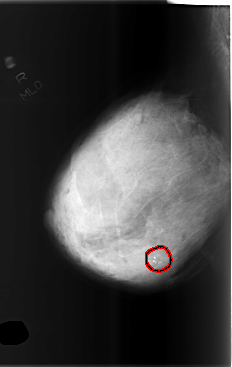

ics_version 1.0 filename C-0505-1 DATE_OF_STUDY 22 12 1998 PATIENT_AGE 57 FILM FILM_TYPE REGULAR DENSITY 4 DATE_DIGITIZED 25 2 1999 DIGITIZER LUMISYS LASER SEQUENCE LEFT_CC LINES 5728 PIXELS_PER_LINE 3872 BITS_PER_PIXEL 12 RESOLUTION 50 NON_OVERLAY LEFT_MLO LINES 5784 PIXELS_PER_LINE 3856 BITS_PER_PIXEL 12 RESOLUTION 50 NON_OVERLAY RIGHT_CC LINES 5800 PIXELS_PER_LINE 3936 BITS_PER_PIXEL 12 RESOLUTION 50 OVERLAY RIGHT_MLO LINES 5872 PIXELS_PER_LINE 3704 BITS_PER_PIXEL 12 RESOLUTION 50 OVERLAY |

FILE: C_0505_1.RIGHT_MLO.OVERLAY TOTAL_ABNORMALITIES 1 ABNORMALITY 1 LESION_TYPE CALCIFICATION TYPE DYSTROPHIC DISTRIBUTION CLUSTERED ASSESSMENT 4 SUBTLETY 5 PATHOLOGY BENIGN TOTAL_OUTLINES 1 BOUNDARY |